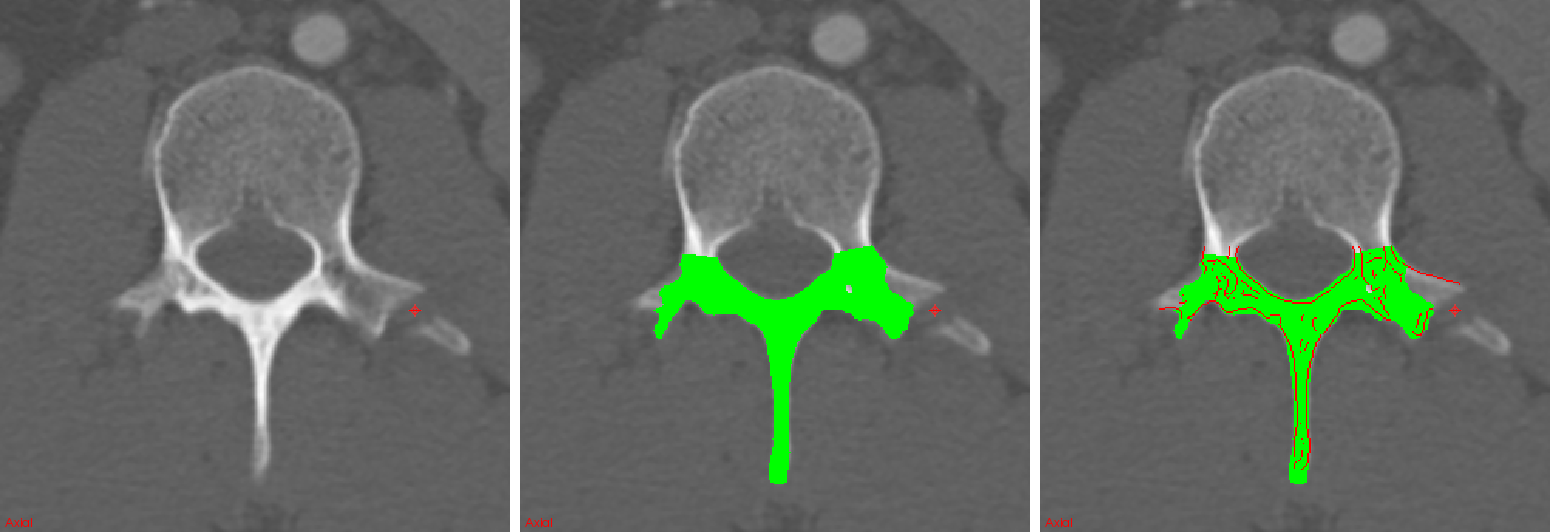

An experienced radiologist retrospectively marked the location of 55 displaced posterior-element fractures in 18 trauma patients admitted for traumatic emergencies to the University of California-Irvine Medical Center. Image sizes range within and resolutions range within mm. We use a random subset of 12 of these patients with spine fractures for training ConvNets as described in Section 2; 6 patients are reserved for testing. An additional set of 5 spine CTs of healthy patients were added to the training set in order to increase the number of non-fractured examples. A total of 800,000 2.5D patches are randomly selected from the candidate edge maps of the training set and used for learning the ConvNet parameters. After convergence, the ConvNet is applied to a testing case edge map E in order to produce a probability map for fractures. Figure 5 shows examples of probability maps for posterior-element fracture detection along candidate edges. The radiologist’s markings are indicated by crosshairs.

![]() |